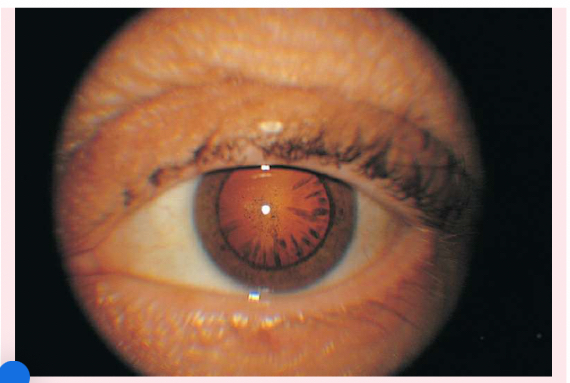

Nuclear cataracts

appear gray when seen with a flashlight; they appear as a black spot against the red reflex

Peripheral cataracts

look like gray spokes that point inward when seen with a flashlight; they look like black spokes that point inward against the red reflex when seen through an ophthalmoscope.